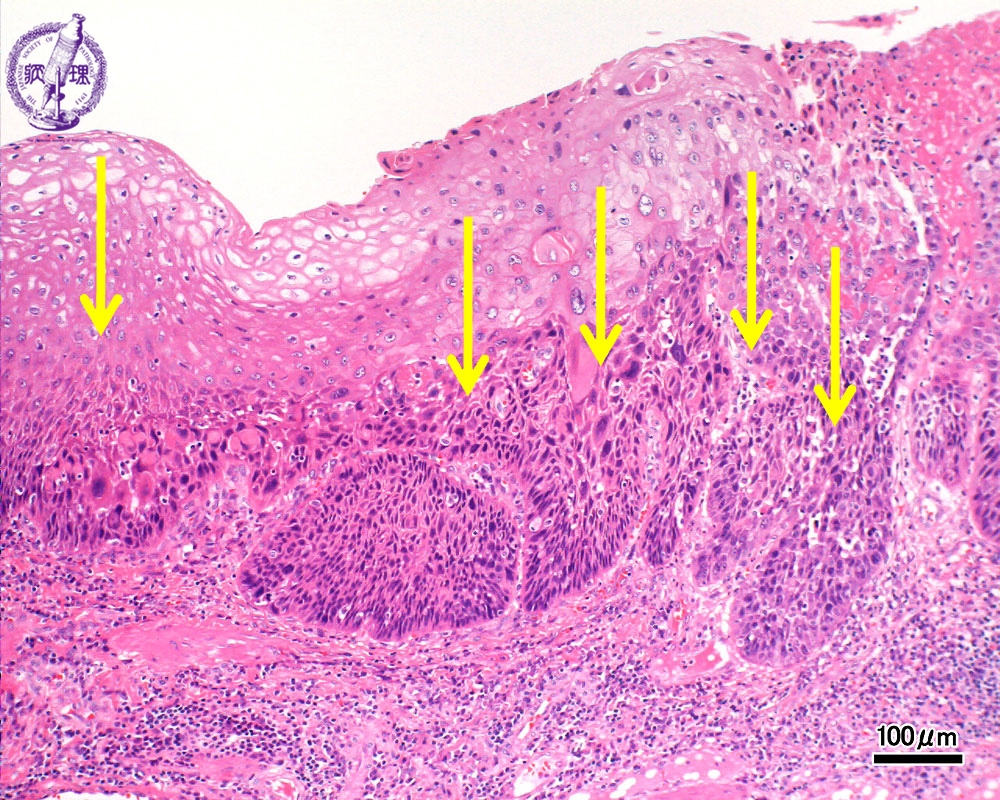

- ★(3)Esophageal carcinoma (squamous cell carcinoma)

Microscopic view (H&E stain, intermediate power): The basilar epithelium is occupied by atypical cells which show expansive invasion into the lamina propria (squamous cell carcinoma, arrow).